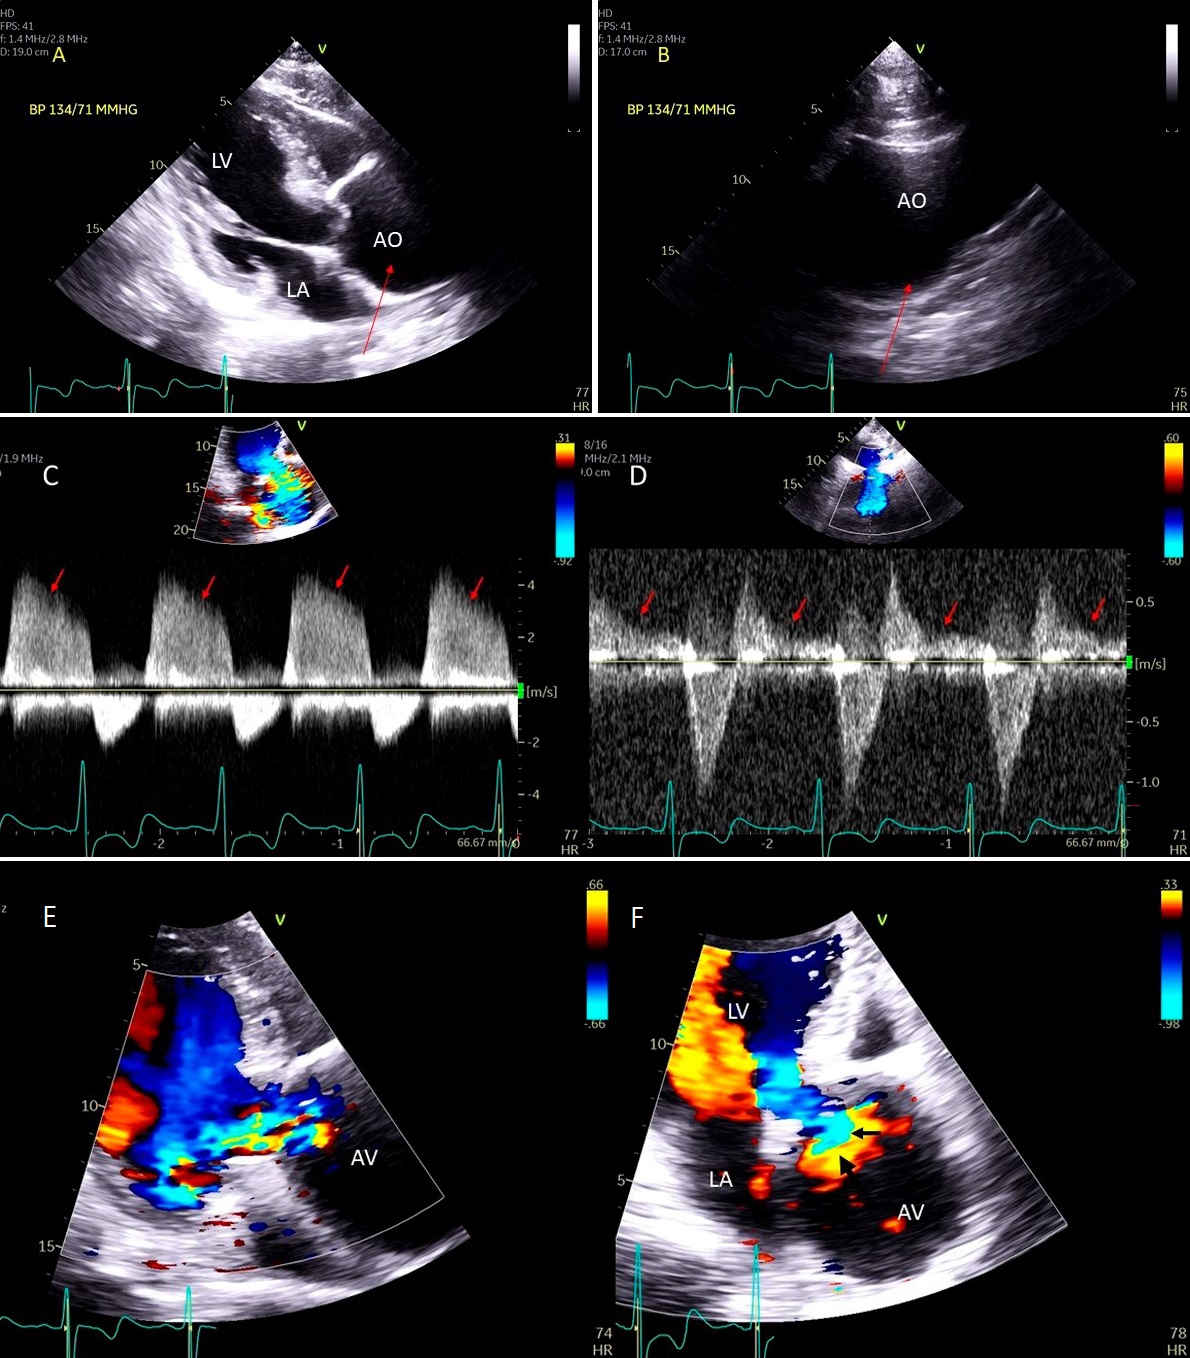

These criteria are generally more reliable in central jets. Pulmonary artery systolic pressure, mitral inflow E wave velocity and pulmonary vein flow pattern are other helpful parameters. Systolic pulmonary vein reversal (Fig. 1) is highly specific for severe MR but is not very sensitive. Discrepancy may occur between MR ERO and RV in mitral valve prolapse in early stages of MR where non holosystolic MR jet duration and hence regurgitant volume are smaller than the PISA derived EROA which does not account for the duration of MR jet. 2D vena contracta width may be unreliable in eccentric jets, however direct measurement of regurgitant orifice can be done using 3D color Doppler vena contracta area which may allow better quantitation of MR in central as well as eccentric MR jets [5] as well as in patients with multiple MR jets in whom PISA quantitation by adding multiple jets has not be validated and in whom continuity equation cannot be performed [6].

Fig. 1.Degenerative MR due to Flail posterior mitral valve leaflet. (A) TEE 4 chamber view showing a flail posterior mitral valve resulting in a severe anteriorly directed mitral regurgitation jet. LA, left atrium; LV, left ventricle; AML, anterior mitral leaflet; PML, posterior mitral leaflet. (B) TEE 4 chamber view color Doppler showing anteriorly directed mitral regurgitation with PISA (red arrow). AML, anterior mitral leaflet; AV, aortic valve. (C) Pulsed wave Doppler showing left upper pulmonary vein systolic flow reversal. (D) 3D TEE enface view of the mitral valve from the atrial perspective demonstrating P2 flail scallop with torn chordae. Aortic valve is a 9 o’clock position. AML, anterior mitral leaflet; PML, posterior mitral leaflet.